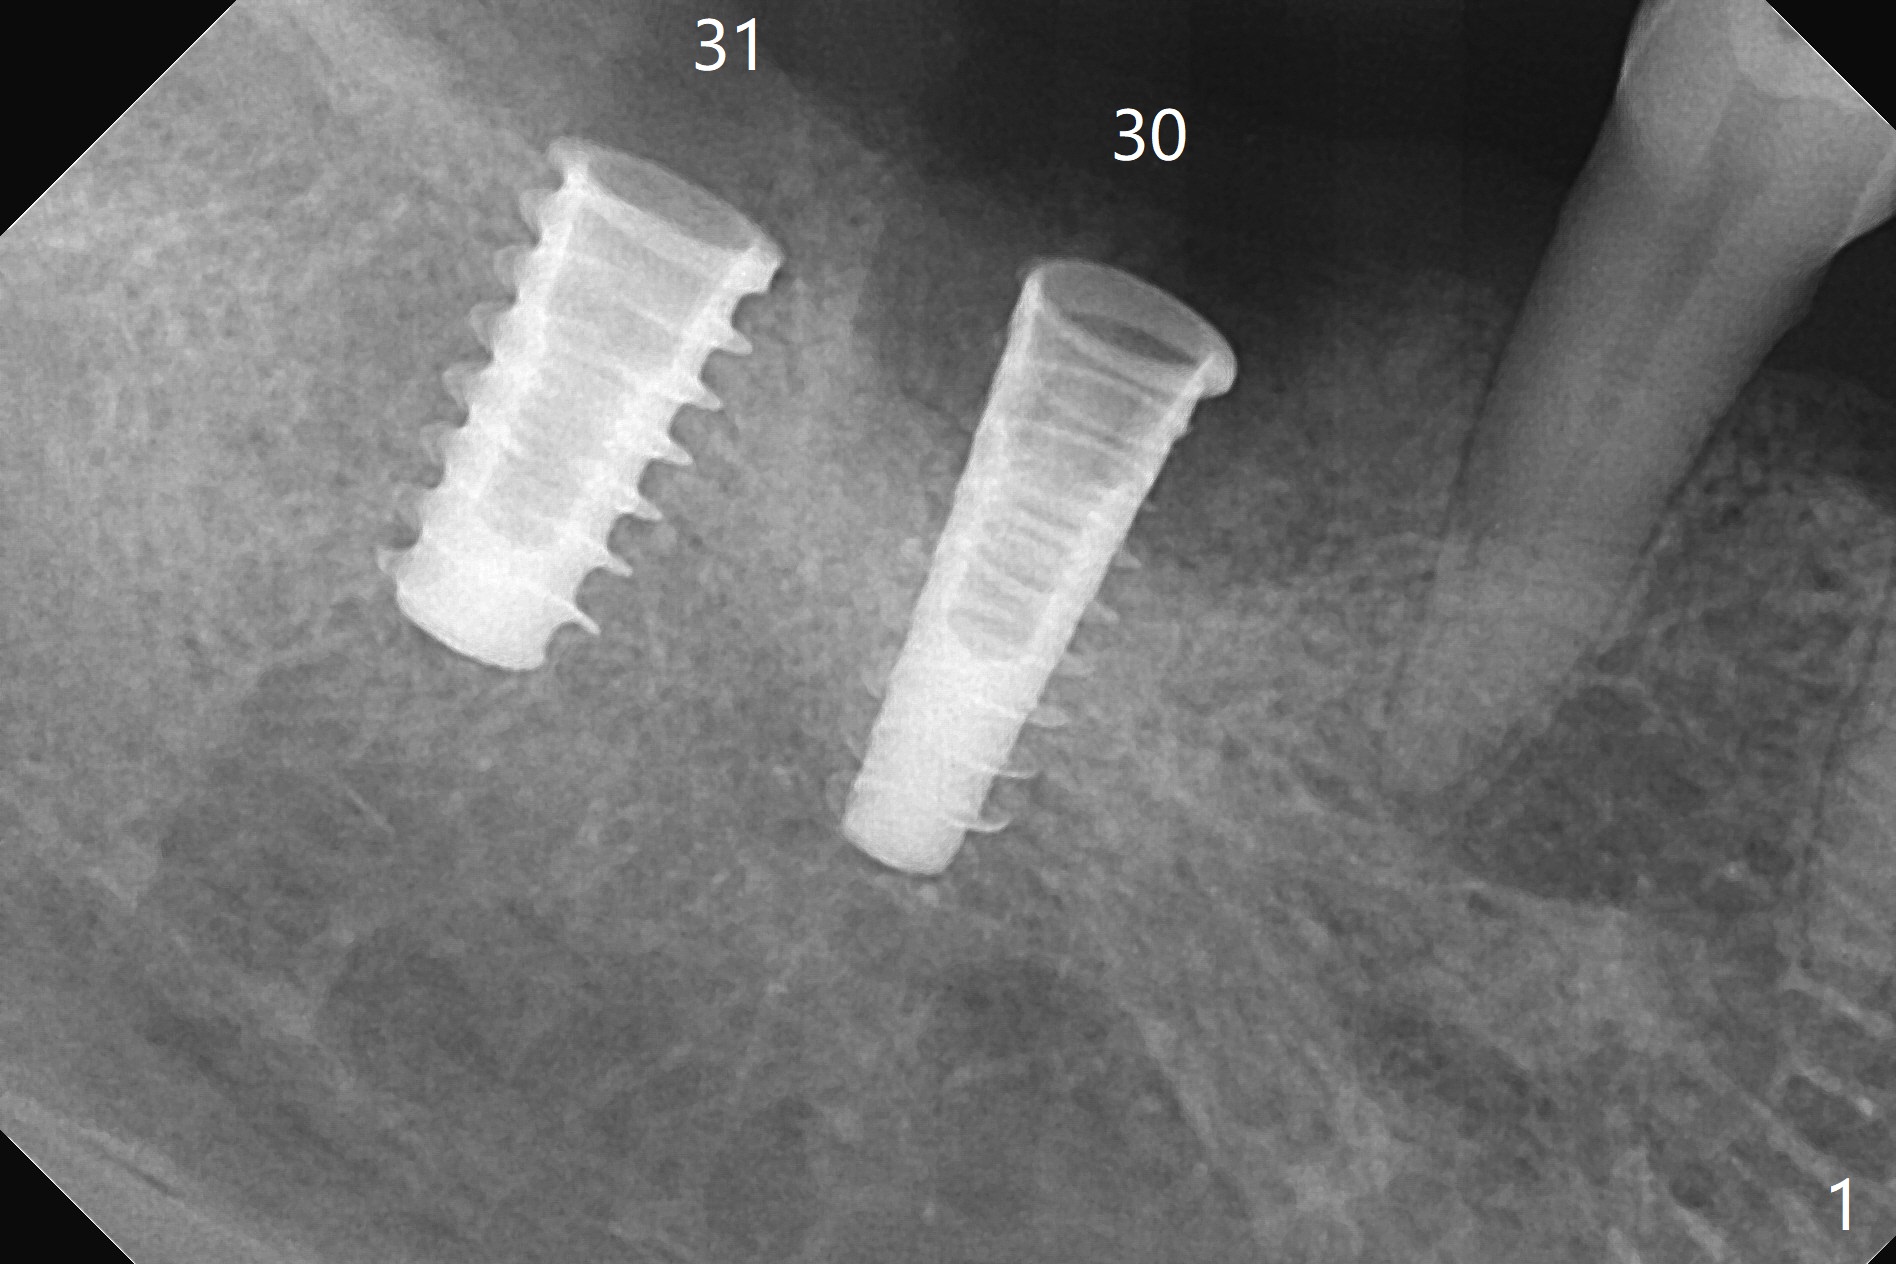

Following osteotomy, 4.5x11 and 5x9 mm dummy implants are placed at the sites of #30 and 31, respectively (Fig.1).  Due to limited inventory of Magicore and patient's in-cooperation, FC implants (4.5x9 and 5x9 mm) are placed (Fig.2).  A healing abutment (6x4 mm) is placed at #31 because of low torque (overprep), while a pair abutment (6.5x5.7(4) mm) is placed at #30.  Vera Graft is placed with autogenous bone (*).  The implant/abutment ratio at #30 is unfavorable.  If the implant turns out to be loose, immediate implant should be larger in the future.  Note bone growth, especially at #30, 2.5 and 4 months postop (Fig.3,4).  In fact the abutments are incompletely seated.  The crown of #30 is loose 2 years 8 months post cementation, while the abutment at #31 remains incompletely seated (Fig.5).  The latter is completely reseated after separating the crown, while a smaller one is seated at #30 (Fig.6) due to use of a small healing abutment earlier (Fig.5).  A good piece of news is the presence of the bone between the implants (Fig.5,6 *), which contributes to interimplant papilla.  Return to Lower Molar Immediate Implant, Prevent Molar Periimplantitis (Protocols, Table), IBS77, 2-5 Xin Wei, DDS, PhD, MS 1st edition 09/22/2017, last revision 12/01/2020